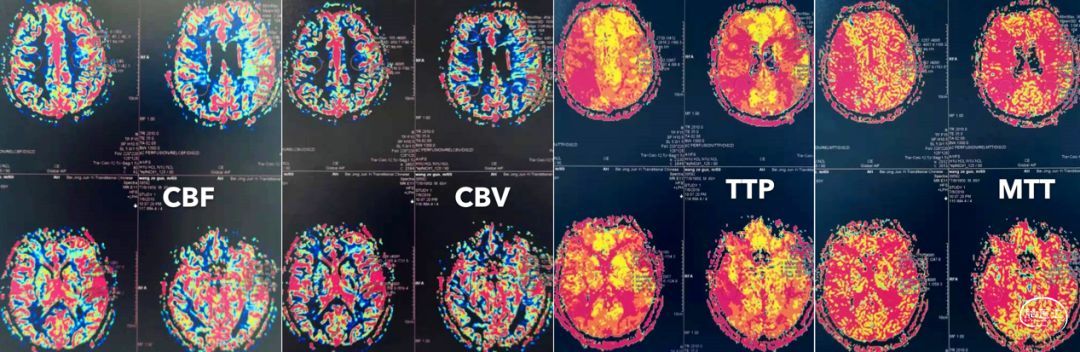

入院后,我们补充了几项检查,包括灌注、高分辨核磁,并复查造影。灌注提示:右侧半球CBF降低、TTP和MTT延长。但由于左侧MCA狭窄,所以并不非常显著。

当地医院灌注检查提示:右侧半球灌注不足。